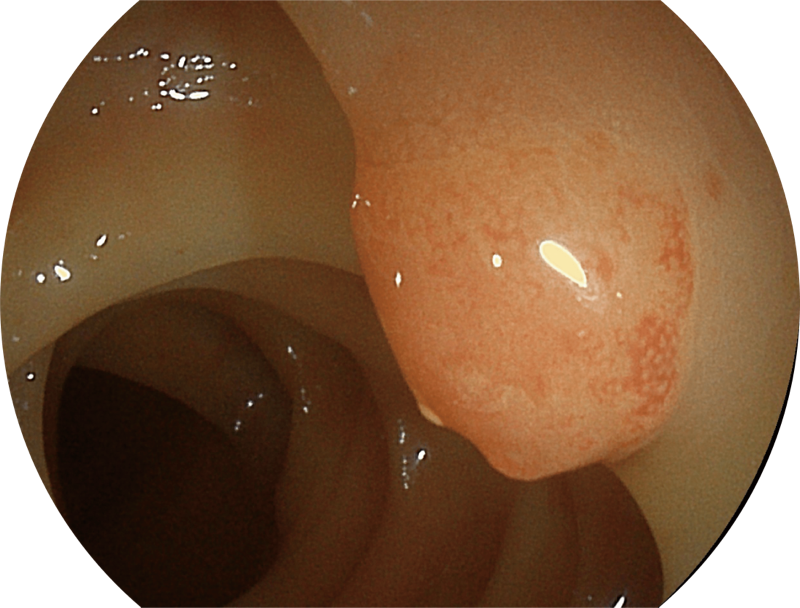

百万级像素高清传感器,1080P全高清视频信号输出,图像清晰。